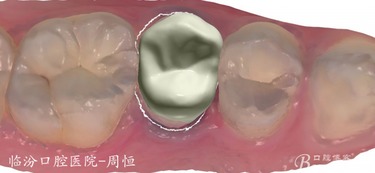

嵌體位于牙體內(nèi)部,只能修復(fù)缺損的牙體組織,不能保護剩余的牙體組織。

嵌體在咬合受力后會將力傳導(dǎo)至洞的側(cè)壁,在剩余牙體內(nèi)產(chǎn)生拉應(yīng)力,過大的拉引力會造成牙體折裂。 要避免咬硬物,注意勿進食過硬食物,以免因給牙齒帶來過大的負(fù)荷而影響嵌體的長期使用。

嵌體位于牙體內(nèi)部,只能修復(fù)缺損的牙體組織,不能保護剩余的牙體組織。嵌體在咬合受力后會將力傳導(dǎo)至洞的側(cè)壁,在剩余牙體內(nèi)產(chǎn)生拉應(yīng)力,過大的拉引力會造成牙體折裂。